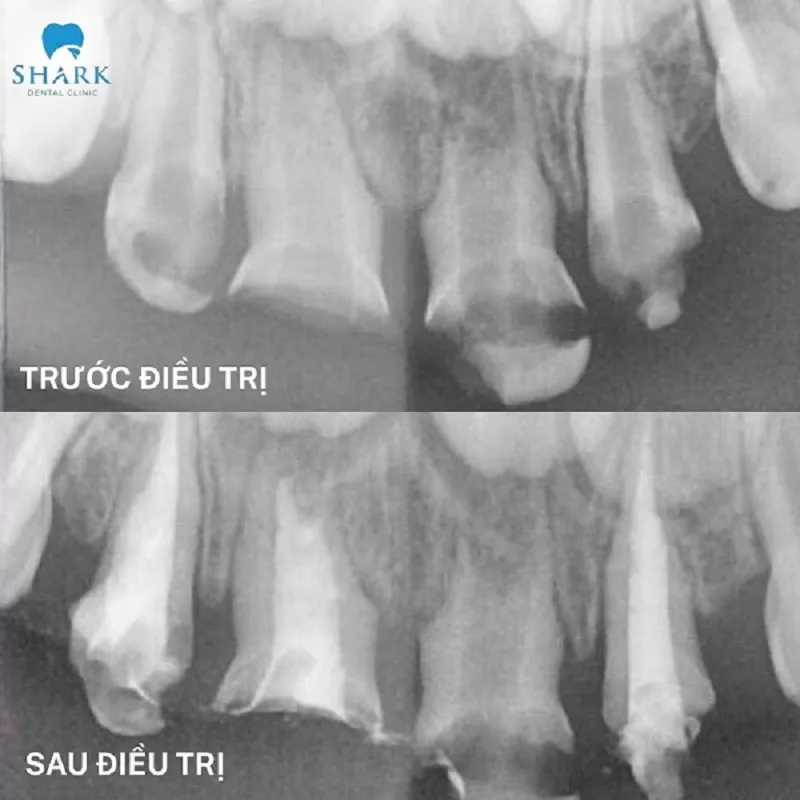

Before and After Comparison

To clearly demonstrate the effectiveness of this method, please refer to the comparison table below, which outlines the conditions before and after root canal treatment:

| Pulp condition | Necrotic pulp tissue with spreading infection | Pulp tissue removed; no signs of infection |

| Surrounding Tissue Damage | Possible pus-filled bumps or abscess causing infection | Infected bacteria around the root apex gradually decrease and disappear |